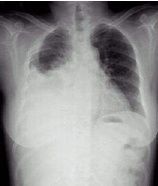

病史:男性,65岁,突感胸闷气促1小时。诊断:

○ 右侧气胸

○ 右侧大叶性肺炎

○ 右侧胸腔积液

○ 肺结核

○ 右侧肺癌